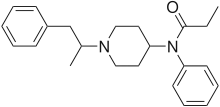

Anilidopiperidines

- 3-Allylfentanyl

- 3-Methylfentanyl

- 3-Methylthiofentanyl

- 4-Phenylfentanyl

- Alfentanil

- α-Methylacetylfentanyl

- α-Methylfentanyl

- α-Methylthiofentanyl

- Benzylfentanyl

- β-hydroxyfentanyl

- β-hydroxythiofentanyl

- β-Methylfentanyl

- Brifentanil

- Butyrfentanyl

- Carfentanil

- Fentanyl

- Lofentanil

- N-Methylcarfentanil

- Mirfentanil

- Ocfentanil

- Ohmefentanyl

- Parafluorofentanyl

- Phenaridine

- R-30490

- Remifentanil

- Sufentanil

- Thenylfentanyl

- Thiofentanyl

- Trefentanil

Structures